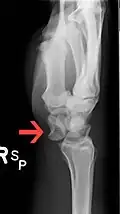

Dislocated lunate -